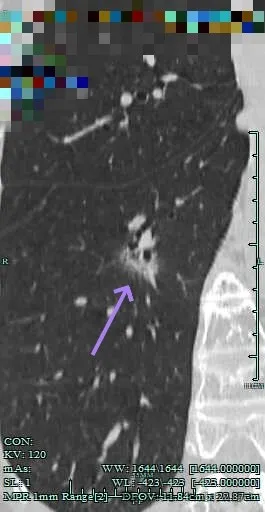

沿支气管走行方向延伸,磨玻璃密度,且支气管内壁显得毛糙。

靶重建显示混合密度,边缘毛糙,内部杂乱,灶内支气管通气且僵硬。

病灶影响到斜裂肺门部,边缘毛刺明显。灶内支气管僵硬。

密度杂乱,毛刺明显,支气管僵硬。

斜裂根部有增厚并与病灶连着。考虑是肿瘤已经侵及叶间裂。